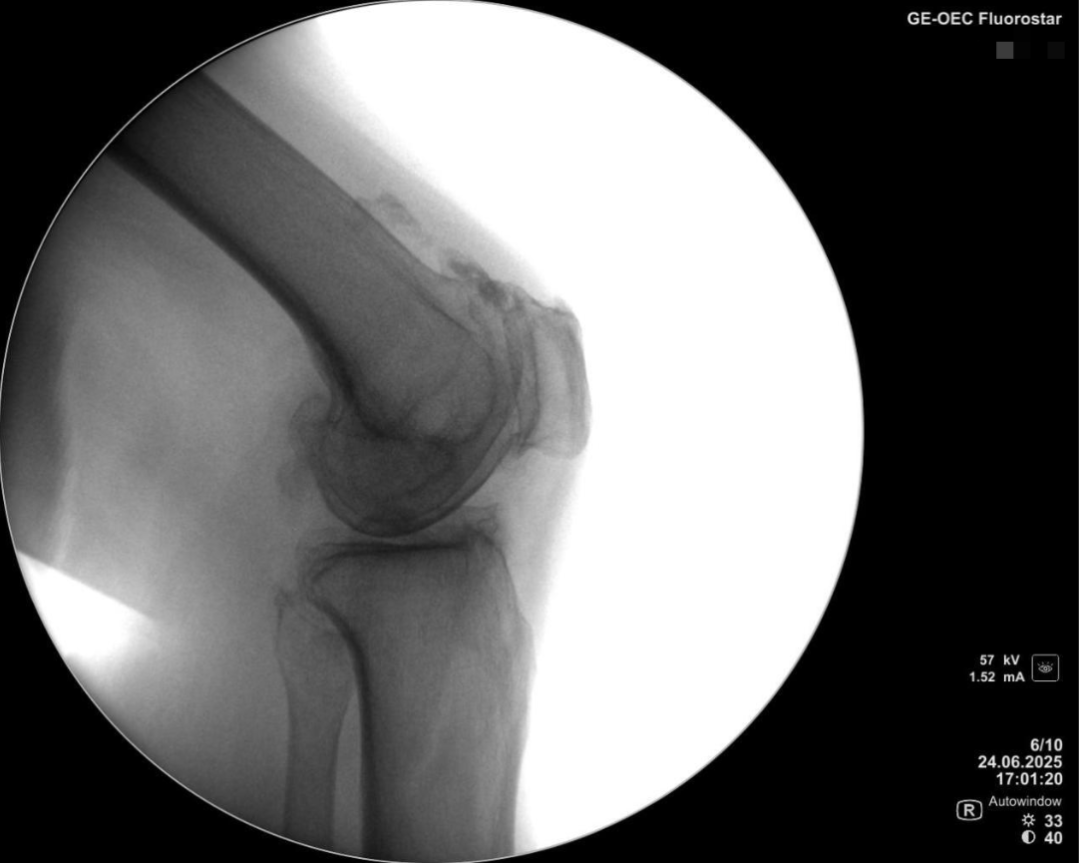

术前透视片